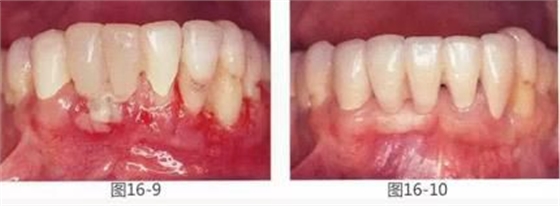

圖16-9 術(shù)后1周。

圖16-10 佩戴最終修復(fù)體時。